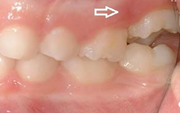

Vali sind huvitav pilt ja me näitame sellega seotud haigust ja sümptomeid